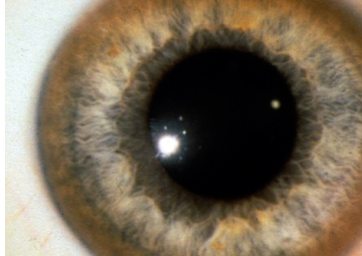

Case 9

A 26 years old female presented with dystonia. O/E is found to have ascites due to portal hypertension & asymptomatic golden brown rings around the corneo-scleral junction (limbus) of the eyes as shown

-

What you see in Pic ? Kayser Fleischer

Diagnosis?: Wilson’s Disease

Treatment: Z

Penicillamine -

What is the type of inheritance for this disease?

- Autosomal recessive

Mention 2 recognized hepatic complications of this disease?

- Chronic active hepatitis

- Liver cirrhosis

Mention 2 tests commonly used for diagnosis of this disease? Z

- Serum ceruloplasmin

- Urine copper

Mention 2 neurological manifestation of this disease? Dystonia, Spasticity, grand mal seizure, wing beating tremor

Name a drug commonly used for the treatment of this disorder? Use of chelating agent for lifelong (penicillamine trientine)

Name a life threatening complication of this disease? Fulminant hepatic failure, Liver cirrhosis